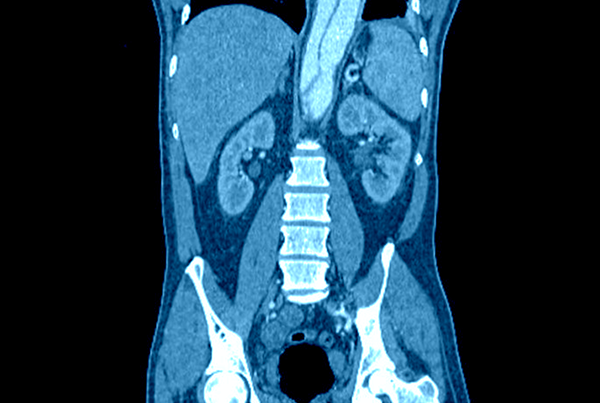

Magnetresonanztomographie (MRT), Computertomographie (CT)